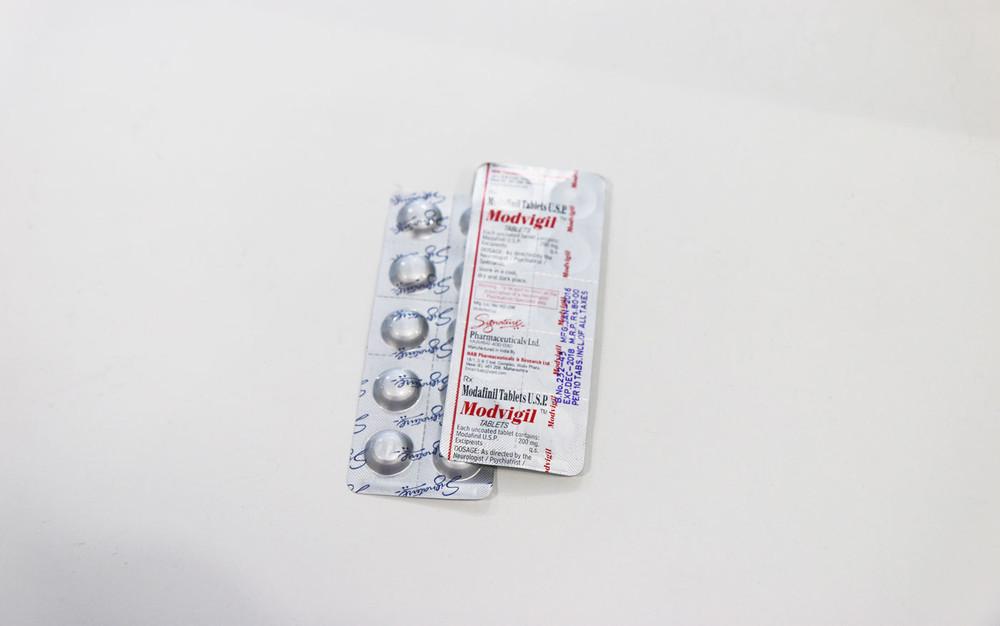

The 'Limitless Pill' Could Soon Turn Us All into Superhuman Workers | VICE | United States http://buff.ly/1P6wDmX pic.twitter.com/gupud7rjc8

02:30 ಅಪರಾಹ್ನ - ಜೂನ್ 4,2016 · ವಿವರಗಳು26 ಮರುಟ್ವೀಟಿಸುವಿಕೆಗಳು 73ಇಷ್ಟಗಳು